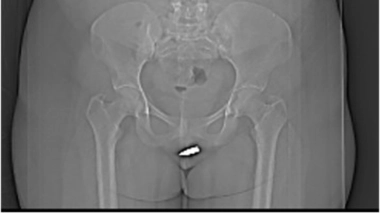

Le clitoris a longtemps été le mal-aimé des organes génitaux féminins. Absent des manuels scolaires, il est pourtant le seul organe uniquement dédié au plaisir. Il se situe en avant de la vulve, à la jonction des petites lèvres et caché par les grandes lèvres. Le "bouton de rose" est doté d'une anatomie beaucoup plus complexe qu'il n'y paraît. La partie visible est composée du gland, partiellement recouvert par un prépuce. Elle est riche en récepteurs, ce qui en fait une zone extrêmement sensible aux stimulations… Le gland se prolonge par le corps, qui se poursuit à l'intérieur de l'organisme de la femme, par une double arche. Celle-ci est composée des corps érectiles, à l'instar du pénis : les corps caverneux et les bulbes se gorgent de sang, sous l'effet de l'excitation sexuelle. Ainsi le clitoris a-t-il une véritable érection, même si sa taille augmente peu…